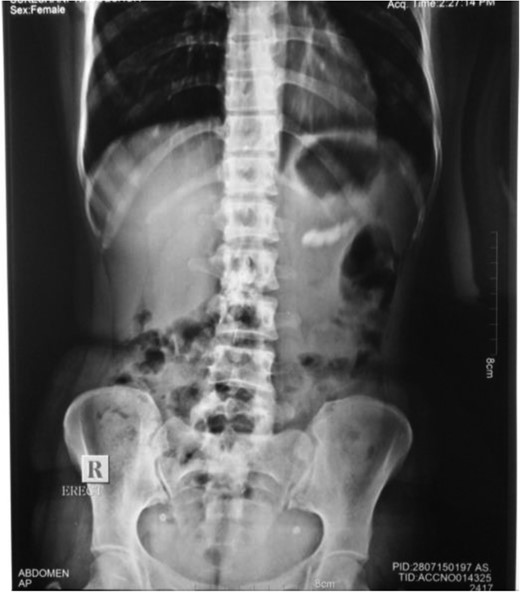

Radiograph showing multiple radio-opaque shadows corresponding to the distal part of pancreas.